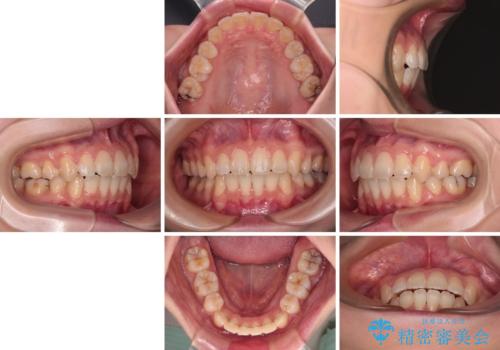

【モニター】口が閉じにくい 抜歯矯正で口元を引っ込める

- 前歯のデコボコや口元の突出感、口の閉じにくさを気にして来院された患者様です。

上下左右第一小臼歯4本を抜歯し、ワイヤー装置にてデコボコを解消しながら口元を引っ込めるよう矯正治療を行うこととしました。

抜歯スペースを閉じている過程で、左側の上下犬歯が引っかかってしまい、進捗が停滞しましたが、当初予定の2年~2年半の間で無事に治療を終えることができました。